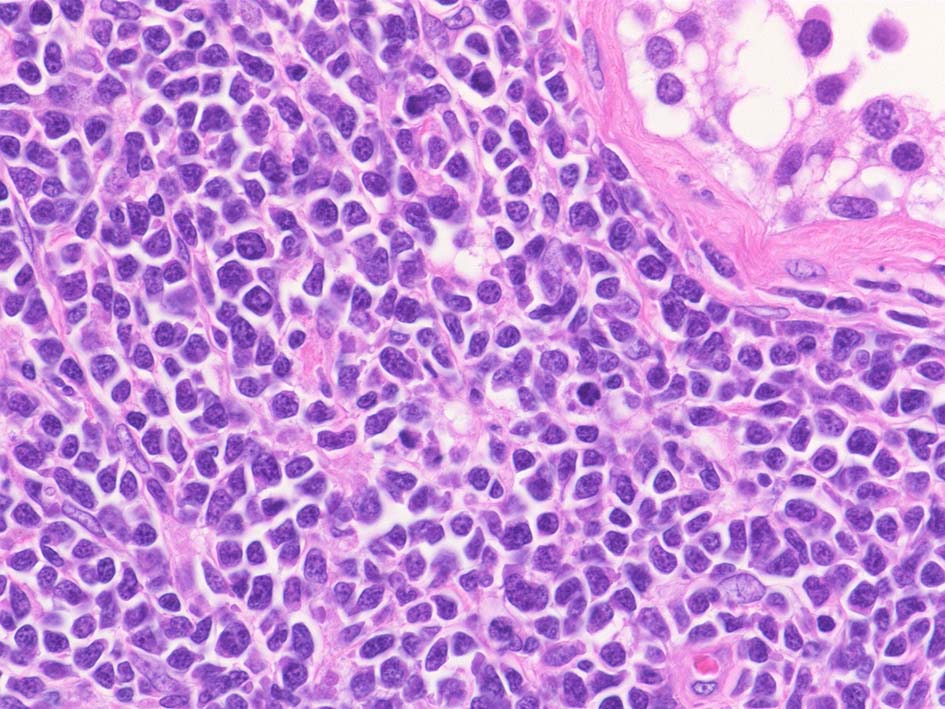

小リンパ球と同程度か1.5倍くらいのサイズ, round/ convoluted nucleiをもつリンパ球がシート状密に増殖する. 核クロマチンは粗で, 核小体が認められる核もある.

DLBCLとは細胞の大きさや細胞所見が異なっている. 精細管への浸潤, 占拠所見がある.